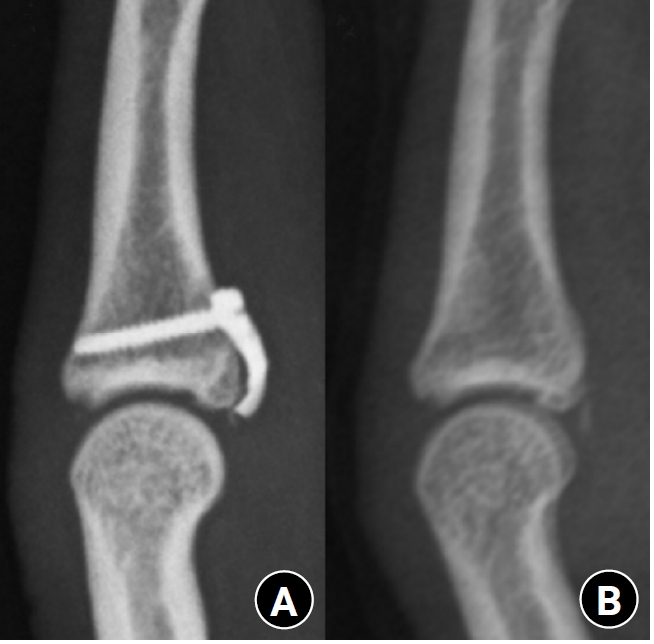

Fig. 2.

Radiographs of a middle phalanx avulsion fracture. (A) Initial fracture. (B) Reduction after open reduction.

Fig. 2. Radiographs of a middle phalanx avulsion fracture. (A) Initial fracture. (B) Reduction after open reduction.